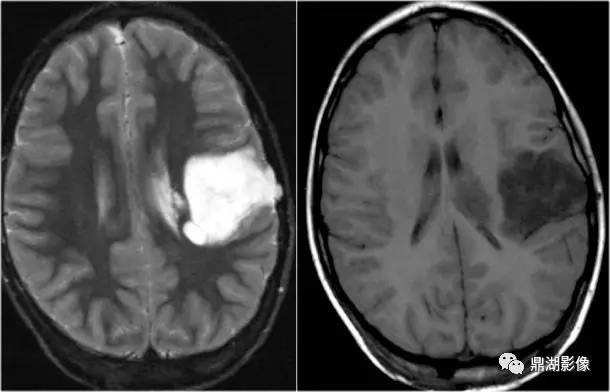

左侧T2WI:我想不用说了吧,不会看磁共振的人都知道,这白白亮亮的是病变。

2.Flair序列(黑水序列)

FLAIR是fluid attenuated inversion recovery的英文缩写,在脑、脊髓MRI(核磁共振)中常用。在T2WI中可抑制脑脊液的高信号,使邻近脑脊液、具有高信号(长T2)的病变得以显示清楚。FLAIR序列属于反转恢复序列(inversion recovery,IR),IR序列是属于获得MRI图像的技术中的序列技术。

T2 FLAIR可以区分游离水与结合水:

在T2 FLAIR序列,游离水呈低信号,如:

而结合水呈高信号,如:

• 实性病变

T2 FLAIR能更清楚显示在常规T2WI被脑脊液高信号掩盖的病变,尤其在脑室周围、脑表面、蛛网膜下腔区域,提高诊断的敏感性。

目前FLAIR+C开始应用于临床,弥补了传统T2加权不能使用钆剂增强扫描。其优势是:

• 消除脑表面血管影的干扰

• 对细小病灶检出率高

• 对细微颅脑外伤具有高敏感性